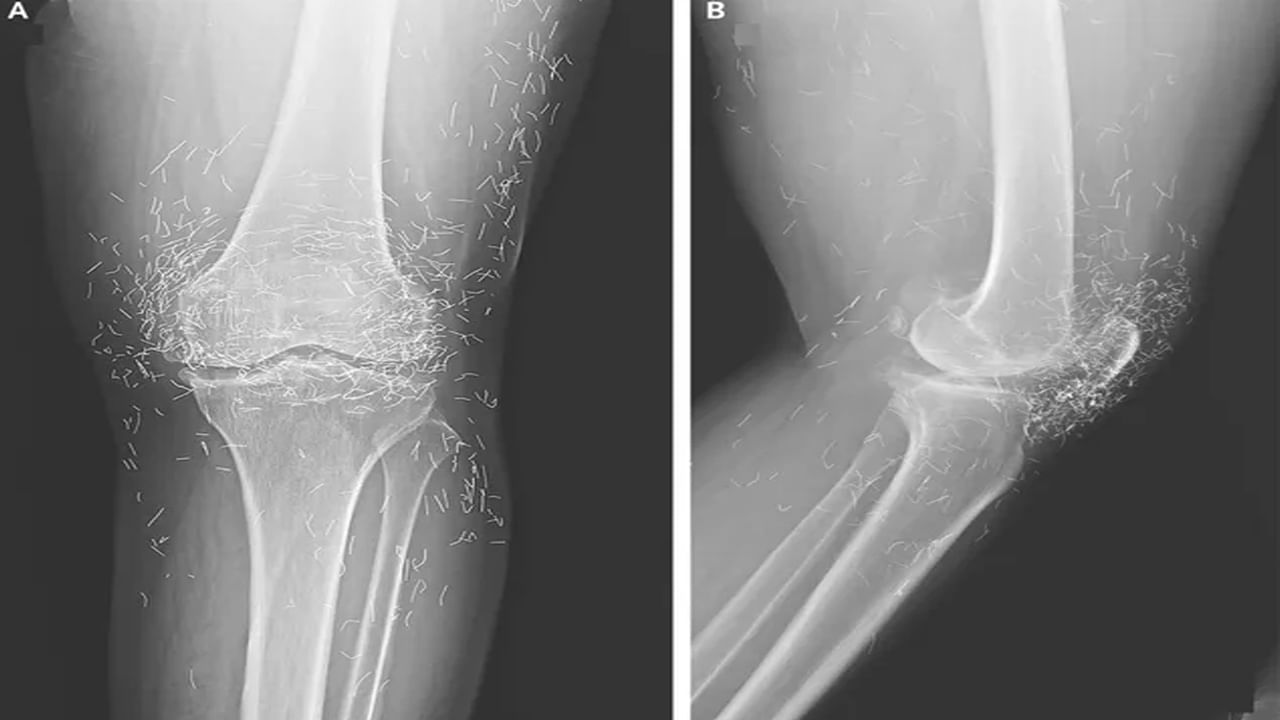

ఆ మహిళ తన కీళ్ల నొప్పులను తగ్గించుకోవడానికి వారానికి ఒకసారి ఆక్యుపంక్చర్ చేయించుకోవడం ప్రారంభించింది . నొప్పి చాలా తీవ్రంగా ఉన్నప్పుడు వారానికి అనేక సార్లు ఆక్యుపంక్చర్ చేయించుకోవడం మొదలు పెట్టింది. అయినా మోకాళ్లు నొప్పి భరించలేనిదిగా మారడంతో మళ్ళీ ఆసుపత్రిలో చేరింది. . వైద్యులు ఆ వృద్ధురాలి ఎడమ మోకాలికి ఎక్స్-రే తీశారు. ఎక్స్-రేలో కనిపించిన దృశ్యం చూసి షాక్ తిన్నారు. అందుకంటే మోకాలి చుట్టూ వందలాది చిన్న బంగారు తీగలు కనిపించాయి. ఈ తీగలు అసాధారణమైనవి కావని.. ‘గోల్డ్-థ్రెడ్ ఆక్యుపంక్చర్’ అనే ఒక చికిత్సా పద్ధతిలో భాగమని గుర్తించారు. అంతేకాదు మోకాలి కీలు లోపలి భాగంలోని షిన్బోన్ మందంగా గట్టిపడిందని చెప్పారు. మోకాలి కీలు దగ్గర షిన్బోన్ , తొడ ఎముక లోపలి భాగాలపై స్పర్స్ అని పిలువబడే ఎముక పెరుగ్తున్నట్లు గుర్తించారు.

ఆసియాలో ఆస్టియో ఆర్థరైటిస్ , రుమటాయిడ్ ఆర్థరైటిస్ రెండింటికీ చికిత్స చేయడానికి గోల్డ్-థ్రెడ్ అక్యుపంక్చర్ను సాధారణంగా ఉపయోగిస్తారని వైద్యులు చెప్పారు. అయితే, ఈ పద్ధతి పనిచేస్తుందని ఎటువంటి ఆధారాలు లేవు.. కొన్ని సందర్భాల్లో ప్రజలు సకాలంలో చికిత్స పొందకుండా నిరోధించడం ద్వారా పరోక్షంగా ఆర్థరైటిస్ను మరింత దిగజార్చుతుందని హెచ్చరిస్తున్నారు. ఈ బంగారు దారాలు శరీరం లోపలకు వెళ్లి.. శకలాలు పొరుగు కణజాలాన్ని దెబ్బతీస్తాయి. ఈ తీగలు శరీరంలోని ఇతర భాగాలలో చేరుకోవచ్చు.. దీనివల్ల తీవ్రమైన ఇన్ఫెక్షన్లు రావచ్చు హెచ్చరిస్తున్నారు.